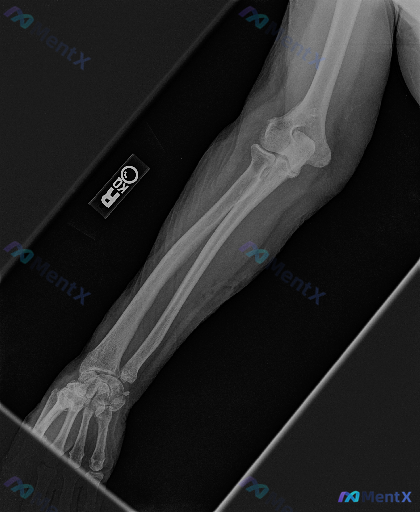

整理到一张放射影像资料,是右侧前臂X光片(正位)。 想请大家先读片,看看这张片子里有没有明确的异常?如果有,你认为最核心、最需要优先关注的是哪一组表现? (注:背景信息暂时先不放,就单看这张影像的表现来讨论)

整理到一份右侧前臂X光正位影像的病例资料,先和大家同步目前可见的表现: 1. 骨骼方面:桡骨远端干骺端区域可见骨皮质中断,远折端有向背侧/桡侧移位的迹象;尺骨茎突处也有骨皮质不连续的表现。 2. 关节方面:桡腕关节的正常解剖关系似乎有改变,下尺桡关节区域看起来间隙不太规整。 3. 软组织:桡骨远端周...

整理到一张右侧前臂侧位X光片的影像资料,大家可以先看看这些表现: 1. 桡骨远端骨干骺端可见骨皮质中断,骨折线通过,伴有背侧成角移位及粉碎性改变 2. 尺骨茎突也有骨皮质中断 3. 腕关节背侧及掌侧有明显软组织肿胀 4. 肘关节对合关系良好,尺桡骨中段皮质连续 5. 骨质密度分布均匀,未见明显骨质溶...

整理到一份右侧前臂及腕关节的X光片影像分析资料,给大家同步一下核心发现,一起讨论后续的评估与观察重点: 病例影像背景 - 拍摄部位:右侧前臂+腕关节 - 已有处理:影像中可见外固定装置覆盖 主要影像学异常 1. 骨骼连续性:桡骨远端可见明显骨折线,骨皮质中断,有断端移位和背侧/桡侧成角畸形,同时伴尺...